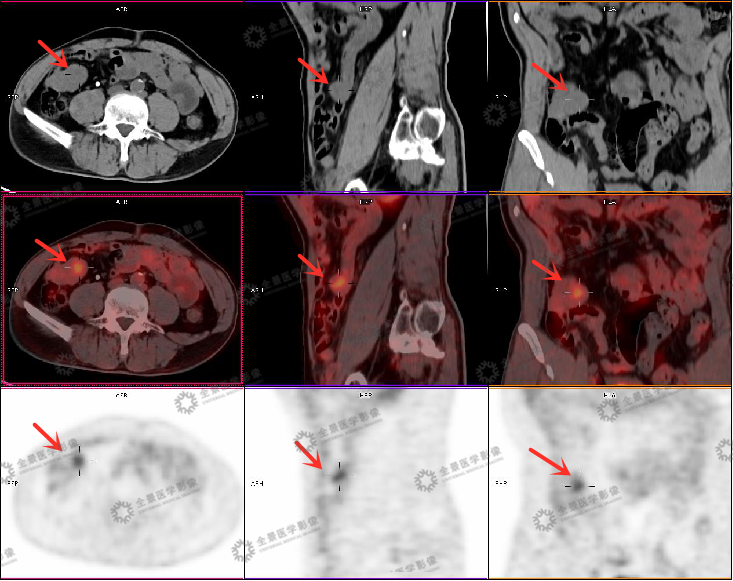

为了进一步查明便血及贫血原因,为李先生安排了PET/CT检查,果然,检查中发现,在回肠腔外有一个软组织肿块伴FDG代谢升高,是一个4厘米左右的肿瘤,幸运的是肿瘤周围未见明显侵犯和转移表现,考虑为小肠间质瘤,结合起病时长及肿瘤大小,考虑已经是低度恶性的可能大,建议尽快接受外科手术治疗。

全景PET/CT发现回肠区域腔外生长型间质瘤